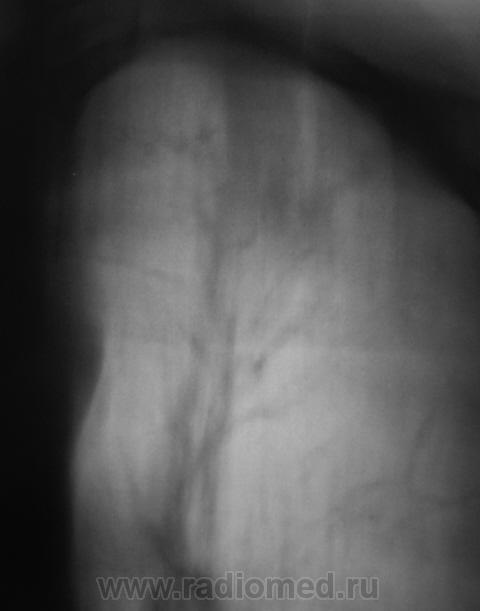

Динамика через 2 месяца после специфического лечения.

Ниже снимки до лечения.

Валентин Львович! Динамика, конечно, слабая. Но "Его Величество" не всегда адекватно реагирует на проводимую терапию. Или это изменения после перенесенного "Его Величества".  Склоняюсь к мысли слабо положительной динамики после проводимой специфической терапии.

Спасибо за высказанное мнение. Мы тоже отметили некоторую положительную динамику.

Считаю, что динамики нет - как был Твс-архив, так и остался...

Пневмосклероз без динамики. Очаговых изменений не видно. Неужели подтвержден туберкулез?

При первичном обследовании туберкулёз подтвержден. Подтвержден и посевом на средах.